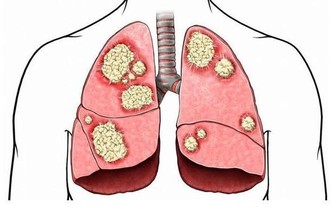

肺臟排毒

蘿蔔是肺臟的排毒食品:在中醫眼中,大腸和肺的關係最密切,肺排出毒素程度取決於大腸是否通暢,蘿蔔能幫助大腸排泄宿便,生吃或拌成冷盤都可以。

百合提高肺臟抗毒能力:肺臟向來不喜歡燥氣,在燥的情況下,容易導致積累毒素。蘑菇、百合有很好的養肺滋陰的功效,可以幫肺臟抗擊毒素,食用時加工時間不要過長,否則百合中的汁液會減少,防毒效果要大打折扣。

按壓肺臟排毒要穴:有利肺臟的穴位是合谷穴,位置在手背上,第1、2掌骨間,當第2掌骨橈側的中點處,可以用拇指和食指捏住這個部位,用力按壓。

排汗解毒:肺管理皮膚,所以痛痛快快地出一身汗,讓汗液帶走體內的毒素,會讓我們的肺清爽起來。除了運動以外,出汗的方法還可以是熱水浴,浴前水中加一些生薑和薄荷精油,使汗液分泌得更暢快,排出身體深處的毒素。

深呼吸:每次呼吸時,肺內都有殘餘的廢氣無法排出,這些廢氣相對於那些新鮮、富含氧氣的空氣來講,也是一種毒素。只需幾個深呼吸,就能減少體內廢氣的殘留。

肺臟最佳排毒時間:肺臟最強的時間是早7點~9點,此時最好能夠通過運動排毒。在肺最有力的時候進行慢跑等有氧運動,能強健肺排出毒素的功能。